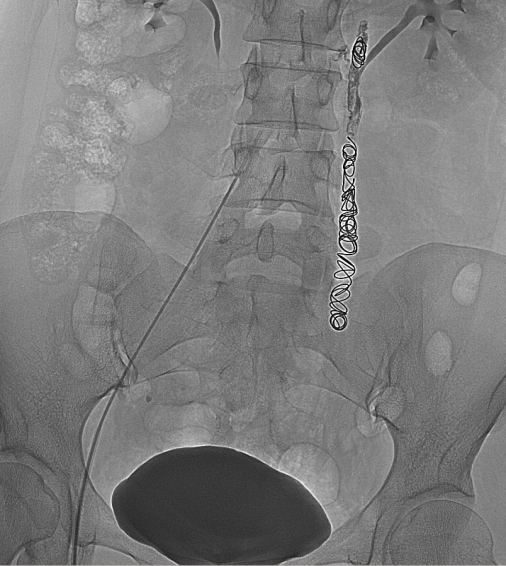

介入治疗是目前公认的盆腔淤血综合征的首选治疗方案。 盆腔淤血综合征的介入治疗是在局部麻醉状态下,通过股静脉穿刺或颈静脉,引入导丝、导管,插入到盆腔静脉,进行盆腔静脉造影及予以硬化剂、金属弹簧圈等予以栓塞,将有病变扩张的盆腔静脉进行封闭,从而达到治疗的目的。 ![]() ![]() 盆腔淤血综合征的介入治疗具有安全性高、创伤小、效果确切、不影响月经及生育的特点。 在四院接受介入治疗后,困扰刘女士四年多的盆腔瘀血综合征终于得到解决,目前已经康复出院。 |